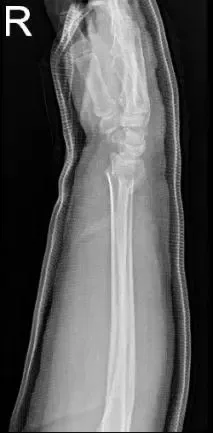

She brought X Ray results for her right elbow with her and has shown prior resection of the right radial head. Mild elbow osteoarthritic degenerative changes. For her right wrist Xray, it showed comminuted angulated distal radial shaft fracture.

Right elbow x-ray